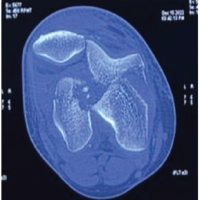

Radiology

X-rays and computed tomography (CT) scan confirmed a neglected posterior dislocation of the right hip with a comminuted fracture of the acetabulum involving the posterior wall and column (Fig. 1-7). The femoral head showed early degenerative changes.